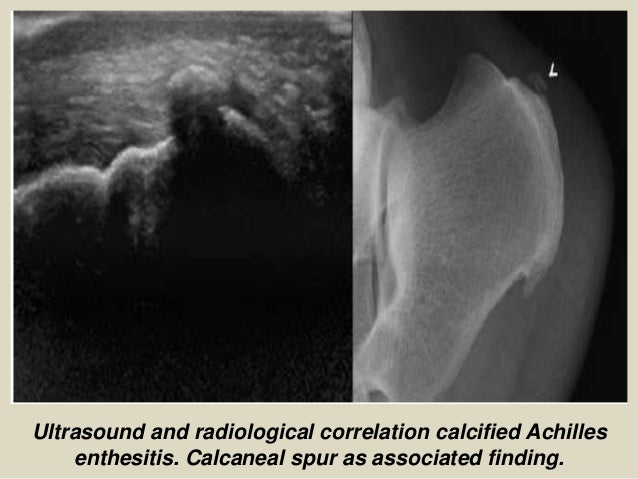

Ultrasound and radiological correlation calcified Achilles

enthesitis. Calcaneal spur as associated finding.

22. 22. Ultrasound and radiological correlation calcified Achilles enthesitis. Calcaneal spur as associated finding.